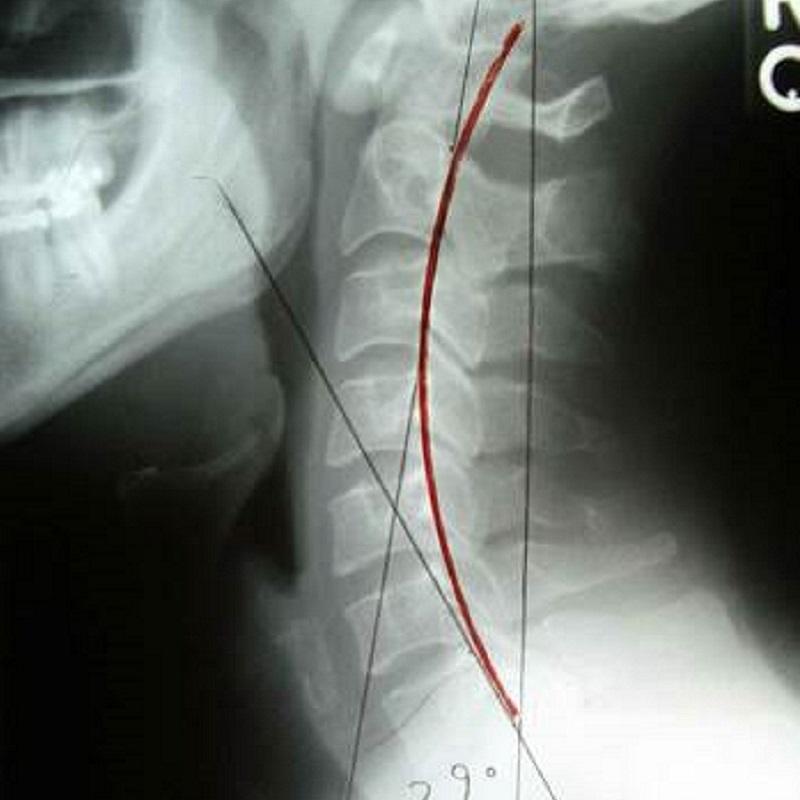

在功能方面,頸椎除支持頭部重量外,更負責協調頭部動作,配合頭部感官器官眼、耳、口、鼻感受環境變化及急機。致病原因如運動創傷或肌肉勞損都可以引起頸痛,寒背姿勢、工作壓力亦可促使頸痛發作。論病理發展,頸部肌肉、韌帶等軟組織傷患與頸椎關節疾患又可以互為因果引致痛症,嚴重者頸正常生理弧度拉直或反張。更甚者,長期頸痛往往伴隨抑郁等情緒病發作。

上頸椎病變可引致上頸椎神經根受壓或產生神經炎症,刺激枕大神經及枕小神經,導致後枕痛、頭側顳部或眉梭位置疼痛,甚或引發張力性頭痛。頸源性頭痛症狀包括頭後枕部牽拉感、頭皮刺痛,上頸椎有相應頸椎錯位或移位,X光張口位檢查亦可上頸椎表現旋轉、偏側或偏移等現象。(延伸閲讀頭痛篇章)